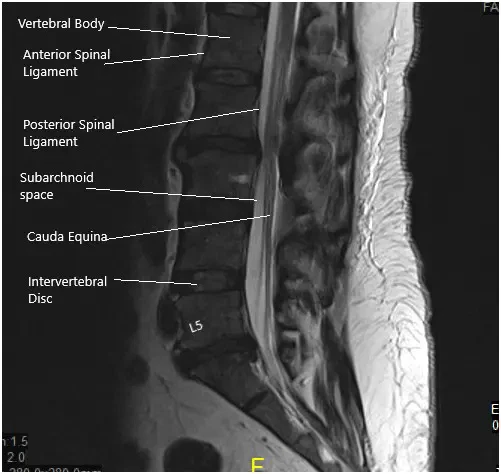

A 50-year-old male patient who started experiencing excruciating pain down his left leg with weakness in that leg and numbness in his peroneal region. His sensory deficit included his lateral thigh and entire foot as well. He obtained an MRI that showed a disk fragment compressing on the L5 and S1 nerve roots with severe lumbar stenosis in the lateral recess and encroachment on the left side at L5 and S1.

Grade I anterolisthesis of L2 on L3. Straightening of the lumbar lordosis. Degenerative changes are identified diffusely within the lumbar spine. At L5-S1, there is a left-sided disc herniation/protrusion causing mild narrowing of the thecal sac and narrowing of the left lateral recess. This encroaches upon the left S1 nerve root within the left lateral recess.

The hernia also extends into the proximal left neural foramen causing mild narrowing. The mild right neural foraminal narrowing is also visualized. Mild to moderate narrowing of the thecal sac is identified at L2-3.

MRI of the lumbosacral spine in sagittal and axial views.